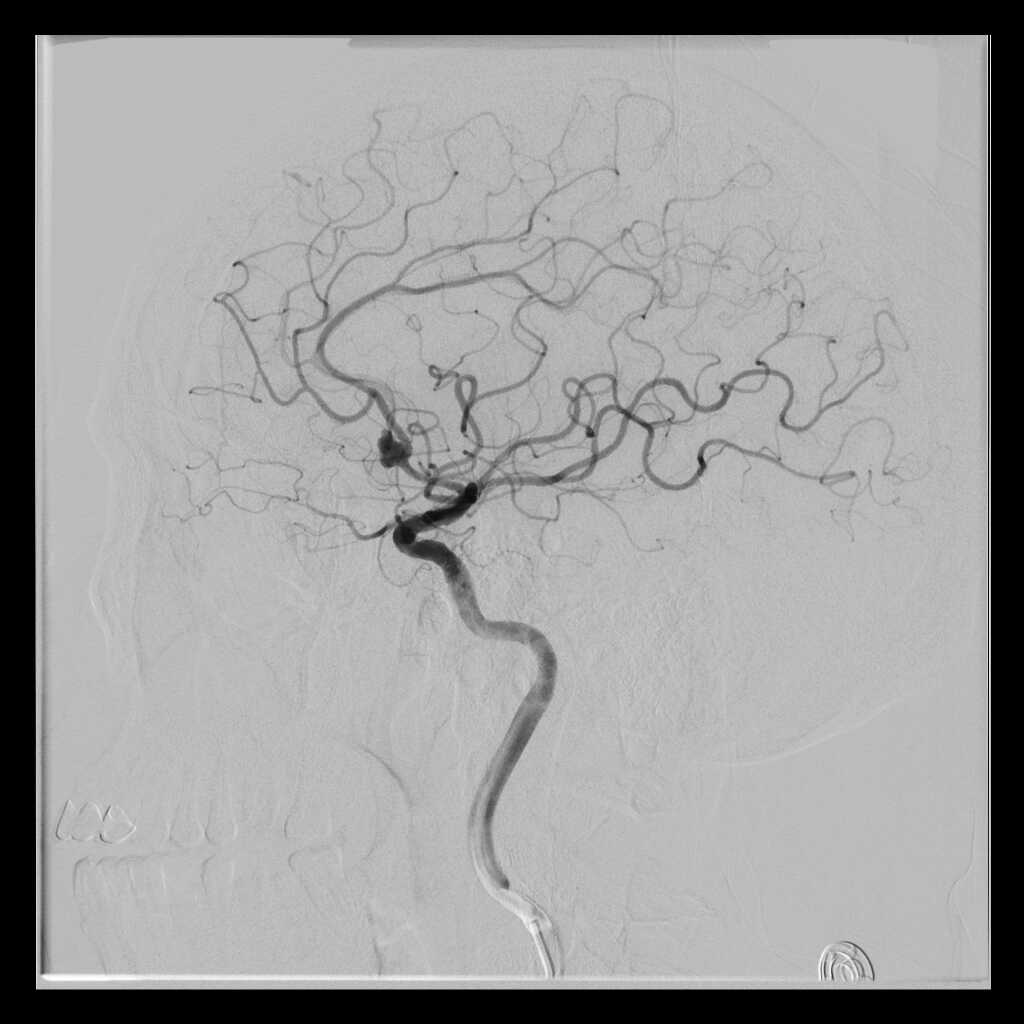

辅助检查

初步诊断:前交通动脉瘤破裂伴蛛网膜下腔出血,低血钾症。

该例患者术中因考虑动脉瘤体大,周围粘连明显,分离较困难,故术中采取低电凝收缩动脉瘤壁后,充分暴露双侧A2,分离动脉瘤与A2之间间隙后再进行夹闭。若术中再多切除部分直回,直接充分暴露双侧A2,再进行瘤壁重塑并夹闭可能更加安全更从容。